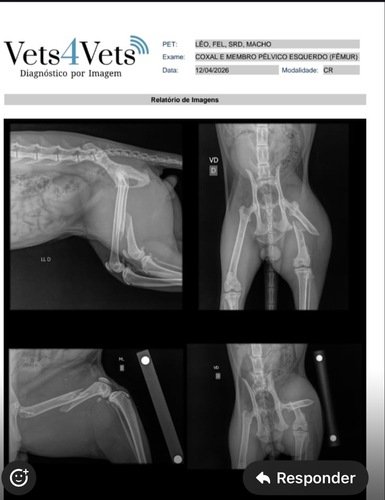

Sou a Aline e junto com meu marido cuidamos de alguns gatinhos da rua de forma voluntária. Um desses gatinhos, o Léo apareceu hoje pela manhã sem conseguir se movimentar e ao levarmos no veterinário foi constatado uma fratura no fêmur com necessidade de cirurgia. Precisamos de ajudar para pagar os custos do tratamento. A cirurgia está marcada para quarta-feira 15/04.